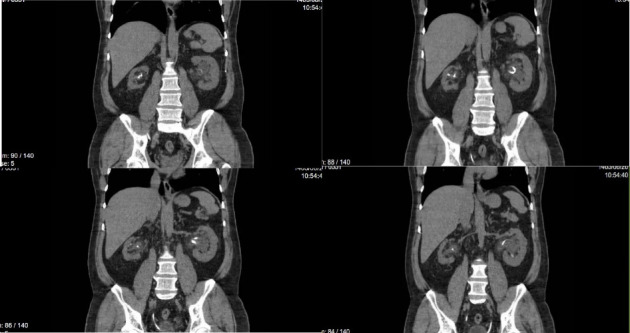

双J (DJ)支架置入术相关的并发症有很好的文献记载,但DJ支架打结仍然是一个极其罕见的事件。我们提出了一个独特的情况下,一个打结和结壳的DJ支架,以及对这一罕见并发症的文献回顾。一名55岁男性,因结石导致输尿管梗阻,最初采用经皮肾造口术(PCN)和DJ支架置入术。患者出现在支架移除的延迟随访后。尽管成像显示没有结痂或打结的证据,膀胱镜尝试移除支架失败。进一步的评估,包括输尿管镜检查,发现DJ支架在肾盂处有明显的结痂和打结。使用半刚性输尿管镜和碎石成功取出支架,无需开放手术。该病例强调了早期随访和患者依从性对预防此类并发症的重要性。当单纯牵引不能取出DJ支架时,应采用先进的内镜技术,如碎石和输尿管镜检查,以有效地处理复杂病例。

Complications related to double J (DJ) stent placement are well documented, but DJ stent knotting remains an exceedingly rare event. We present a unique case of a knotted and encrusted DJ stent, alongside a review of the literature on this rare complication. A 55-year-old man with a history of ureteral obstruction due to stones was managed initially with percutaneous nephrostomy (PCN) and DJ stent placement. The patient presented after a delayed follow-up for stent removal. Despite imaging showing no evidence of encrustation or knotting, cystoscopic attempts to remove the stent failed. Further evaluation, including ureteroscopy, revealed significant encrustation and knotting of the DJ stent at the renal pelvis. The stent was successfully removed using a semirigid ureteroscope and lithoclast without open surgery. This case highlights the importance of early follow-up and patient compliance in preventing such complications. When simple traction fails to remove a DJ stent, advanced endoscopic techniques such as lithotripsy and ureteroscopy should be employed to manage complex cases effectively.